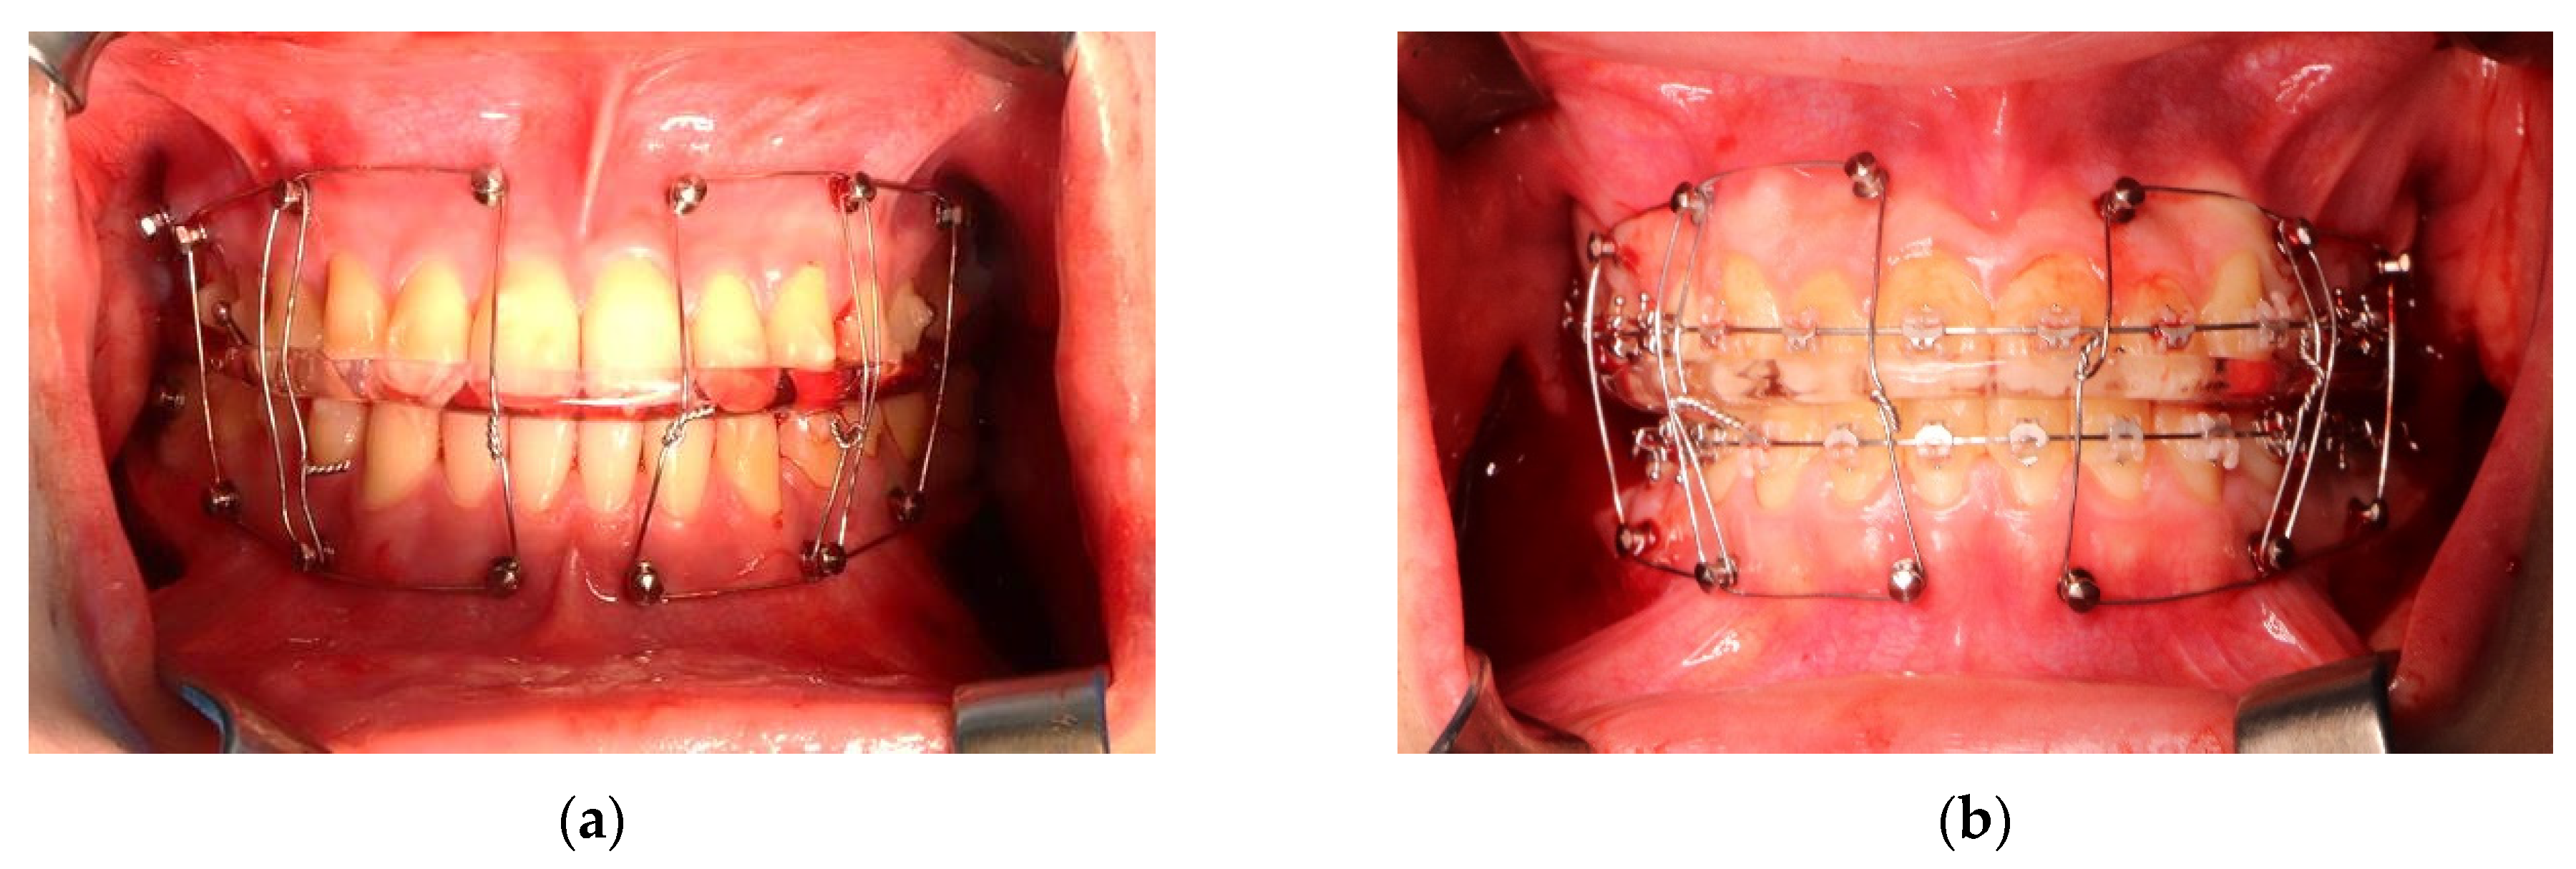

Even though the clear aligner was developed in 1999, it has evolved considerably, and many patients are receiving orthodontic treatment using the clear aligner approach [3,12]. A systematic review on orthodontic treatment using clear aligners found no significant difference in stability and occlusal characteristics compared to conventional orthodontic appliances [13]. Orthodontic treatment with clear aligners has the following advantages, including aesthetics, patient convenience, reduction in the number of visits to the dental clinic, decreased chair time, removable device, convenience in oral hygiene management, saving time required for wire replacement or bracket installation, and ease of taking impressions [2,14]. In addition, the patient is well accustomed to maintaining the device after surgery because they have experience with the device. In addition, there is no interference from braces during surgery (Figure 10), so there is no hindrance during surgery, and there is no risk of the bracket falling off during surgery. Another advantage of orthodontic treatment using clear aligners is that the brackets physically interfere with tooth brushing, making oral hygiene management difficult, but clear aligners do not. These removable clear aligners can also reduce the incidence of white spot lesions on teeth [15]. In a similar vein, according to Sfondrini et al., there was no significant difference in periodontal and microbiological parameters in patients undergoing correction with a clear aligner for two months compared with patients who did not receive orthodontic treatment [16]. According to Kankam et al., there was no significant difference in postoperative edema in orthodontic patients treated with clear aligners [17]. On the other hand, disadvantages include the need to install a screw to anchor the elastics during surgery [18], and the patient’s cooperation during orthodontic treatment is important. According to a large cohort of clear aligner therapy patients, 45.5% of patients wore the aligner for 22 h or more a day, while 25.7% wore it for less than 11 h [19]. Since orthodontic treatment is required after surgery [20], the dentist and the patient must communicate in order to cooperate with the patient, and sometimes the doctor must induce the patient to show better compliance [21]. It must be replaced with the next device according to the requirements, and there is a risk of losing the orthodontic device. Furthermore, braces may be attached during the postoperative orthodontic period.

Figure 10. (a) Intraoperative clinical picture of orthognathic surgery patient with clear aligners. This photo shows the maxillomandibular fixation using wire as a final occlusion state after three mini screws were placed in each segment before fixing the miniplate to the mandible. There are no fixed braces or metal wires attached to the teeth. (b) Clinical pictures of patients who received orthodontic treatment with brackets. The photographing method is the same as in (a).